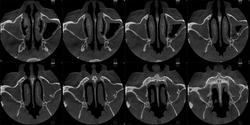

Здравствуйте, коллеги! Представляется КЛКТ ППН. Больной 31 г., направлен ЛОР-врачом на исследование ППН. В левой верхнечелюстной пазухе - костный фрагмент? Аномалия?

На серии изображений прослеживается в задних отделах левой (? ) верхнечелюстной пазухи септальная структура ( вариант строения ), острый синуит ( гайморит), фаза эксудации.

Да, это в левой пазухе.

Эта септальная структура, как мне видится, не связана со стенками пазухи...

Возможно, имеет место не костная, но хрящевая связь. Добавочная септа/перегородка - на мой взгляд, оптимальный вариант. Губчатая остеома выглядит здесь не то что редко, просто незнакомо. На зубик не совсем похоже. Вернее, совсем по-моему не похоже.)